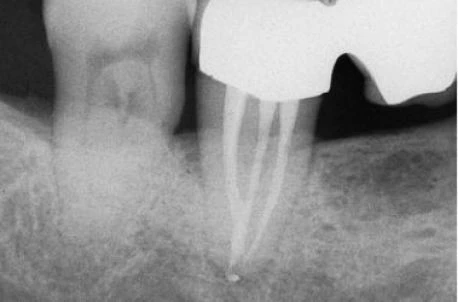

Mở xoang tủy nhìn chung răng cối lớn một hàm dưới có 2 chân phân biệt hình tròn hay thường là elip, ống tủy ở chân xa (hình 11.106) và 2 ống tủy ở chân răng gần. Trong 90% trường hợp chúng đổ ra 2 lỗ chóp khác nhau (hình 11.107) và 10% chúng hợp lại và đổ ra 1 lỗ chóp (hình 11.108).

Hình 11.106. Xoang tủy ở 1 R36: miệng củanhững ống tủy gần khá tròn còn ở ống tủy xa thì thường có hình elip.

Hình 11.107. Các ống gần của răng cối lớn một dưới có những lỗ chóp phân biệt. Chú ý rằng có nhiều ống tủy phụ ở 1/3 chóp (Courtsey of Dr. M. Scianamblo).

Hình 11.108. Các ống gần của răng cối lớn dưới hợp chung lại rồi đổ ra ở cùng một lỗ chóp. Có thể thấy nhiều ống tủy phụ ở chân xa.